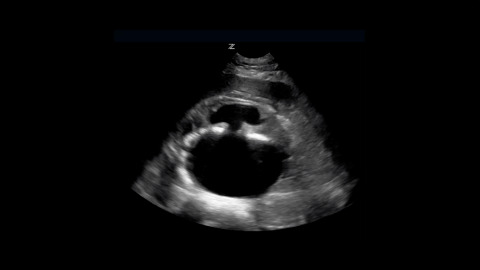

Ruptured AAA

This brief ultrasound clip demonstrates a large abdominal aortic aneurysm that has ruptured.

1 chapterApril 2020